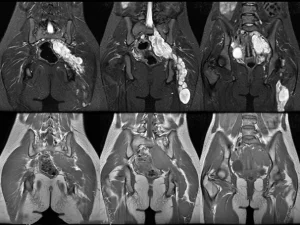

МРТ органів малого таза дозволяє отримати детальне пошарове зображення тканин без променевого навантаження. Дослідження допомагає виявити новоутворення, запалення, ендометріоз, спайки, судинні та структурні зміни. У медичному центрі «Юнімед» МРТ проводиться на сучасному обладнанні, що забезпечує високу точність результатів і допомагає лікарю визначити оптимальну тактику лікування.